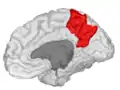

Precuneus

The precuneus is the portion of the superior parietal lobule on the medial surface of each brain hemisphere. It is located in front of the cuneus (the upper portion of the occipital lobe). The precuneus is bounded in front by the marginal branch of the cingulate sulcus, at the rear by the parietooccipital sulcus, and underneath by the subparietal sulcus. It is involved with episodic memory, visuospatial processing, reflections upon self, and aspects of consciousness.

Precuneus of left cerebral hemisphere (shown in red).

Medial surface of left cerebral hemisphere. (Precuneus colored in red.)